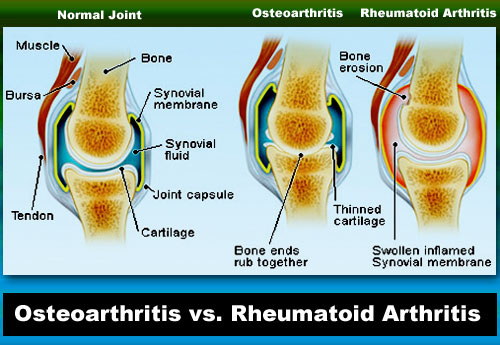

Two of the most common forms of arthritis are Osteoarthritis and Rheumatoid Arthritis.

In a Normal Joint, the muscle and tendon support the bone and aid in movement. The synovial membrane, an inner lining, releases slippery fluid in the joint space between the bones. Cartilage covers the bone ends, absorbing shocks and keeping the bones from rubbing together when a person moves.

In a joint with Osteoarthritis, the cartilage breaks down and the bones rub together. The joint then loses its shape and alignment, and the bone ends thicken forming spurs (bony growths). Bits of bone or cartilage can also float in the joint space.

In a joint with Rheumatoid arthritis, inflammation and thickening of the synovial membrane occurs, causing the whole joint to look and feel swollen. The inflamed joint lining enters and damages bone and cartilage, and they are gradually digested by enzymes released from the inflammatory cells. This is caused by the immune system attacking the body’s own tissues. The joint then loses shape and alignment, and space between joints diminishes.